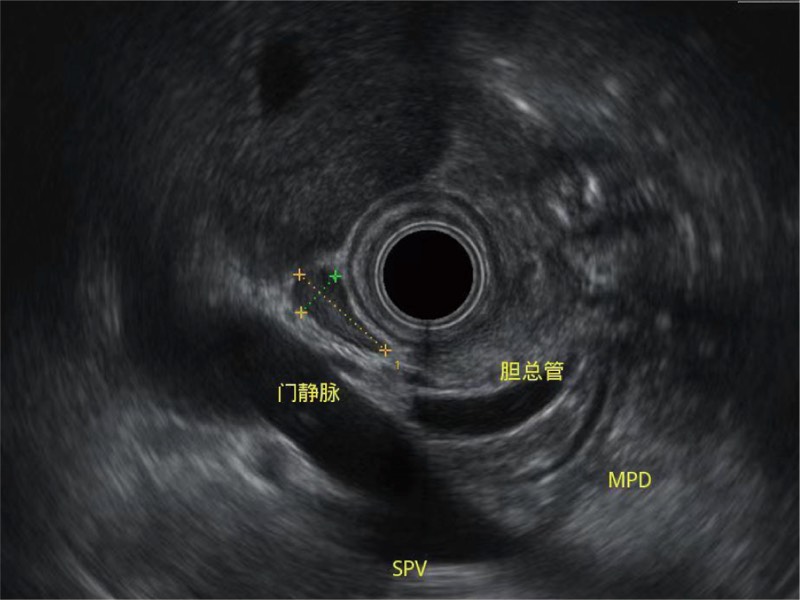

清晰顯示膽總管及周?chē)芊植?/p>